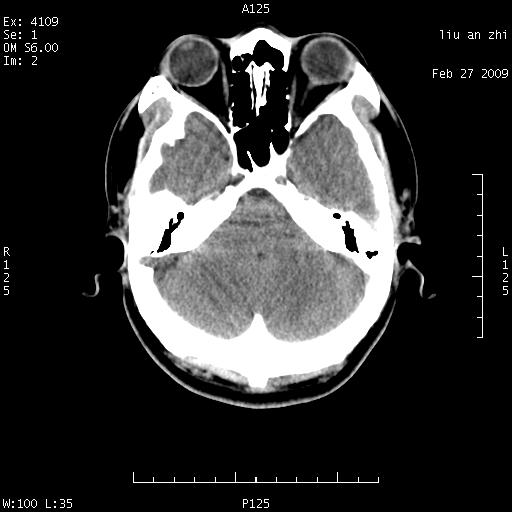

7天后复查头颅ct片:

小脑幕前后7天变化不明显,考虑正常,不考虑sah,7天应该基本吸收了。

ct18448的结果:mri检查左侧天幕下血肿

以下是引用深蓝一号在2009-3-9 16:22:00的发言:[br]ct18448的结果:mri检查左侧天幕下血肿。